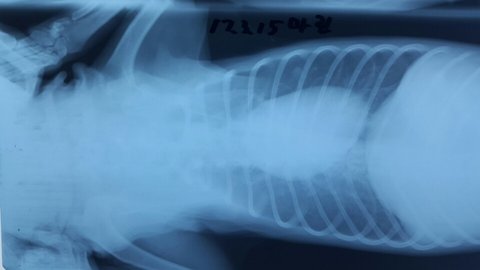

어제 오후 여러 후원자분을 만나 마린이가 씨티와 엠알아이를 찍었습니다.

씨티와 엠알아이 찍기전 기본 혈액검사랑 엑스레이 촬영을 하였고 쪽 앞발 척골이라는 부위에 골절 있으나 수술은 안해도 될 것 같다고 하시네요.

마린인 현재 경추신경 손상이 되었는데 오래된 병변인것 같고 내일정도 되야 정확한 진단을 할 수 있을것 같다고 하시네요.